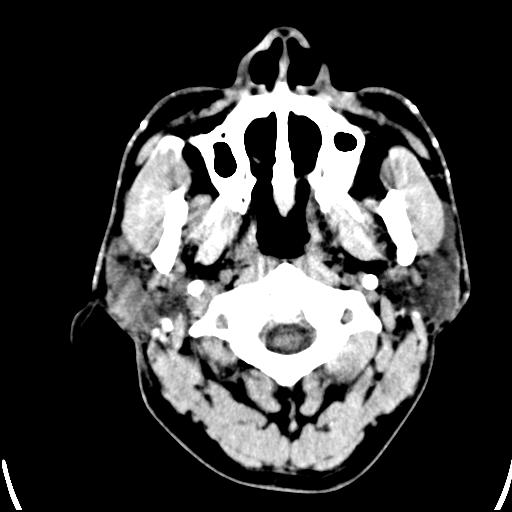

标题: CT25435:头皮下高密度影???

头皮下高密度结节影???临床上在老年男性比较常见。大家看看是什么?成因是? 本例患者,男性,51岁。外伤来诊。无染发史及发根植入史。